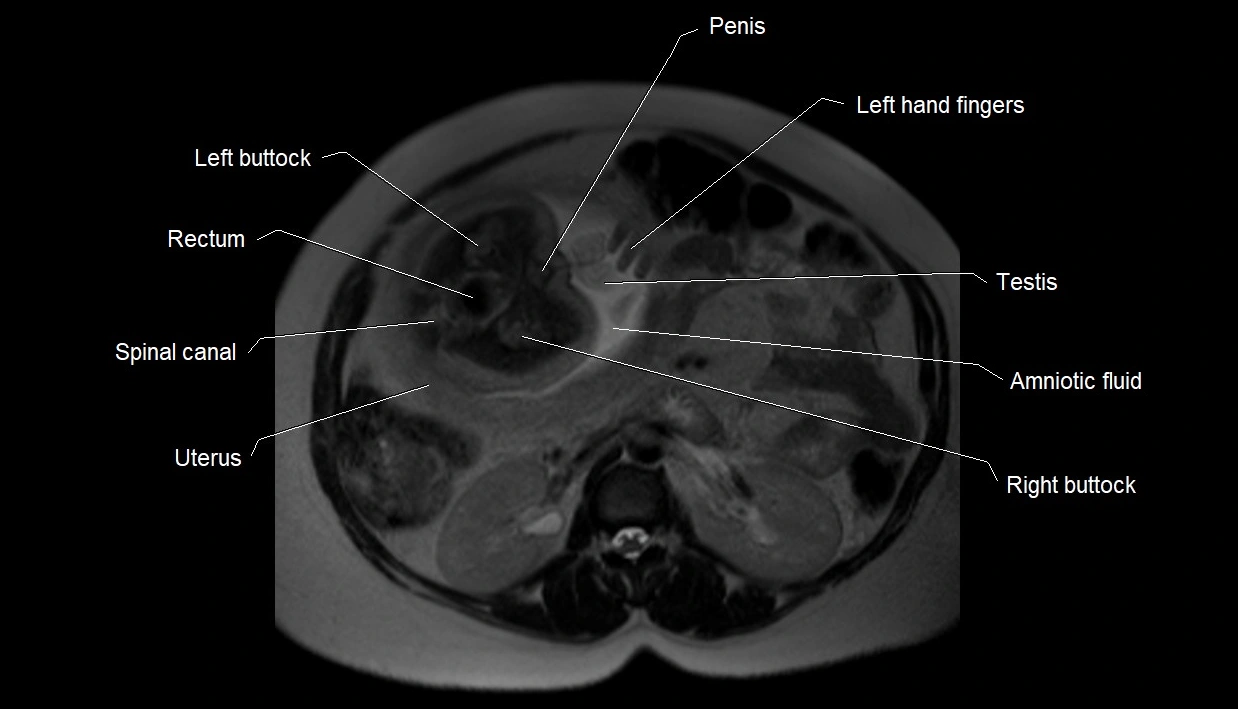

MRI Appearance

T2 HASTE (T2 GRE):

• Amniotic fluid shows very bright hyperintense signal

• Provides natural contrast against fetus and placenta

• Small particles (vernix) may appear as scattered hypointense foci within bright fluid

MRI image

image